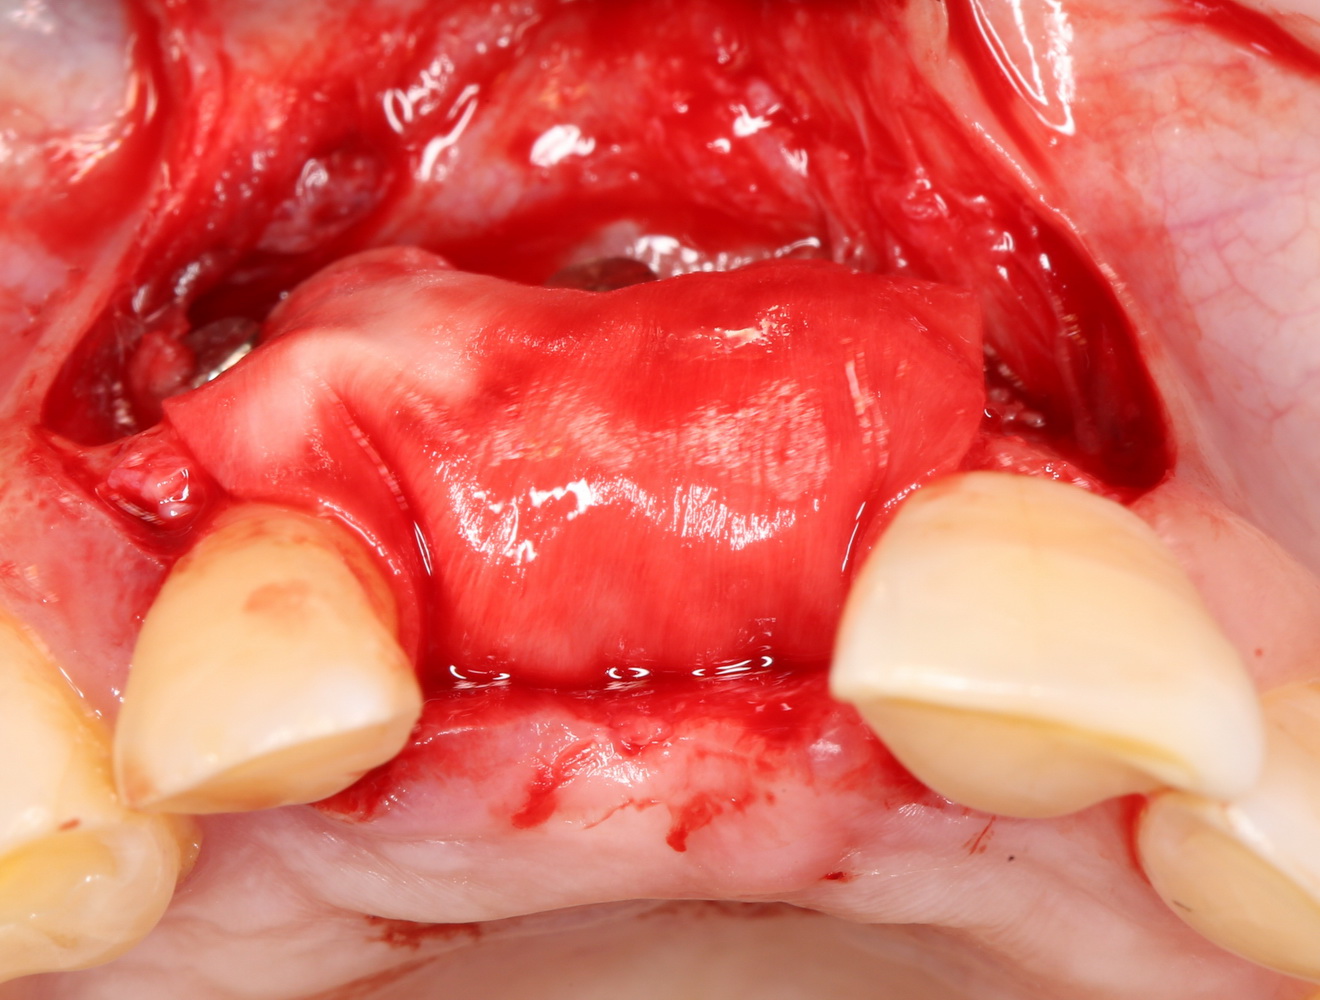

Сначала фиксируется BioGide. Это легко:

Затем укладывается и конфигурируется аутокостная стружка:

Если после этого BioGide намочить физраствором, им легко укрыть получившийся объем:

Для надежности можно зафиксировать пинами: